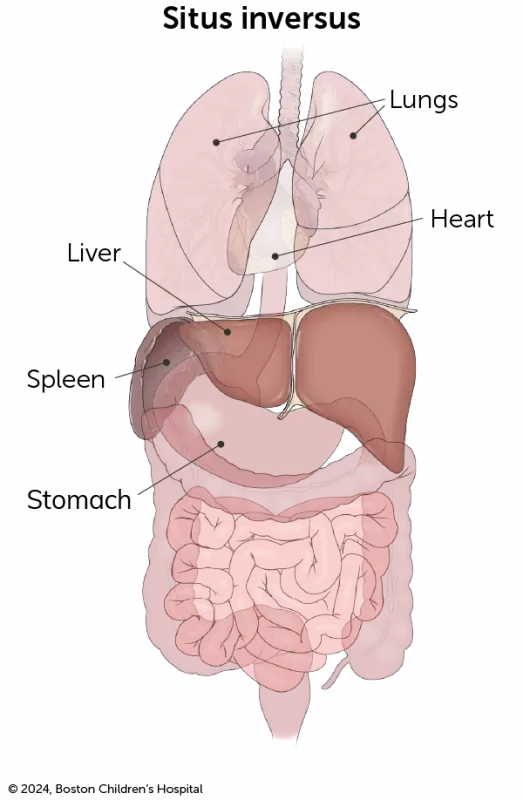

Check out our downloadable pamphlet for a summary about heterotaxy syndrome. It provides details about the diagnosis, testing, treatment at Boston Children’s, and more.